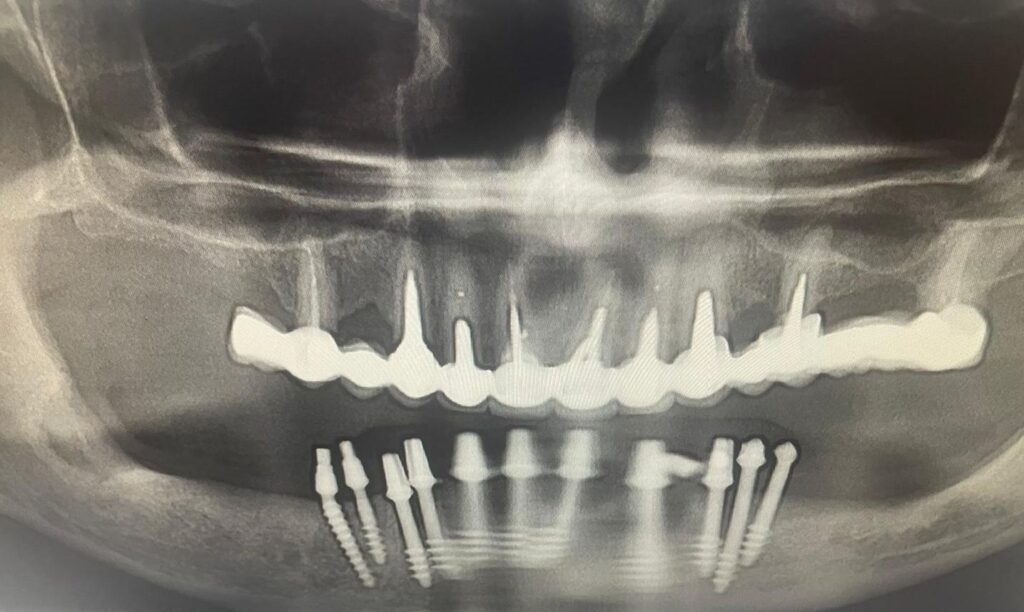

Vă prezentăm un caz mai dificil, deoare pacientul nu avea os. Pentru acest pacient am realizat o lucrare cu implanturi dentare în Bacău. Am efectuat 11 implanturi, în 10 zile fiind realizate atât extracțiile, cât și implanturile dentare și lucrarea definitivă. Aveți mai jos o serie de fotografii din timpul lucrărilor, dar și radiografia dentară, rezultatul este o lucrare cu estetică foarte bună.